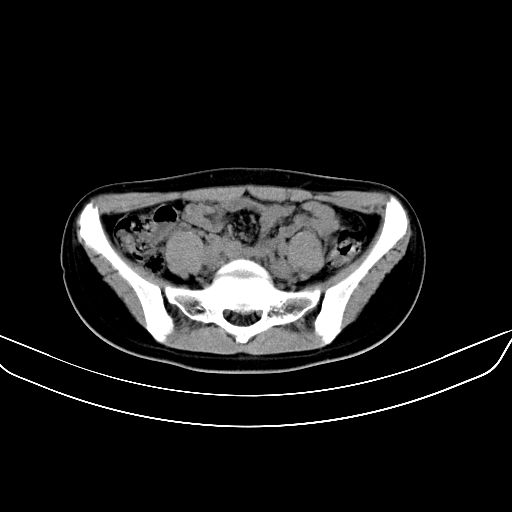

以下是引用zsl6918在2008-7-11 21:40:00的发言:[br]双侧骶髂关节骨质破坏以下三分之一为主,符合强直性脊柱炎表现

以下是引用zhangzhongshou在2008-7-11 21:41:00的发言:[br]患者是女性,hla-b27抗原(—),首先不太考虑强直性脊柱炎,建议查类风湿因子,骶髂关节改变考虑类风湿性关节炎可能性大,建议进一步检查。